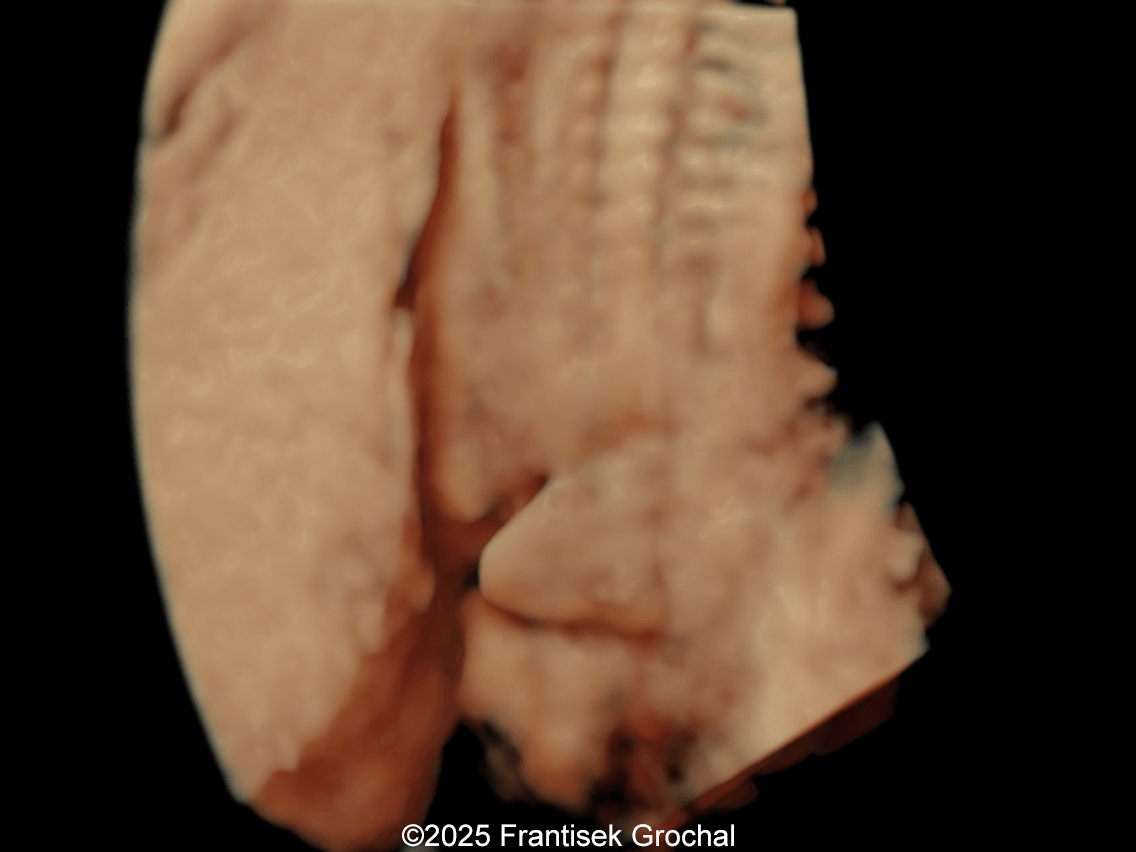

We present a case of Amniotic Band Sequence seen in 21st week of pregnancy. The fetus showed the following findings:

- Bilateral club feet

Prenatal ultrasound imaging shows thin echogenic bands attaching to both the uterine wall and associated fetal structures. The bands themselves can be difficult to detect, hence the visualization of bands is not required to suggest the diagnosis. Random anomalies that do not follow a pattern should lead the clinician to suspect amniotic band sequence and prompt close evaluation for a causative band [5, 6]. The defects resulting from the bands are categorized into various categories: neural tube-like defects, craniofacial anomalies, limb anomalies, abdominal and thoracic wall defects, and visceral anomalies [7, 8]. The most common findings are those caused by constriction rings in the limbs, which are present in at least 80% of cases. They may vary in depth, involving only the skin, to involving bone and causing edema of the distal limb, extremity asymmetry, pseudosyndactyly, or amputation of limbs or digits [8]. Histologically, constriction bands are composed of fibrous tissue containing fibroblasts covered by squamous cells, which may make them inelastic and produce a ligature effect [9]. Clubfoot deformity of the lower extremity is found in up to one third of cases, probably secondary to the presence of oligohydramnios if there is loss of amniotic fluid [6].